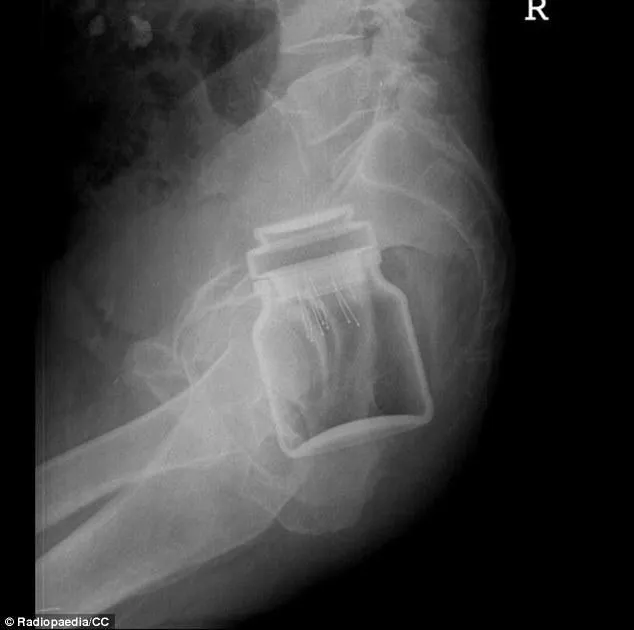

N"ayant pas de jouet coquin sous la main, le patient aurait décidé d"en faire un lui-même en vissant un tube de vitamines sur une bombe de déodorant. Le problème c"est que sa petite fabrication maison est restée coincée à l"intérieur de son rectum.